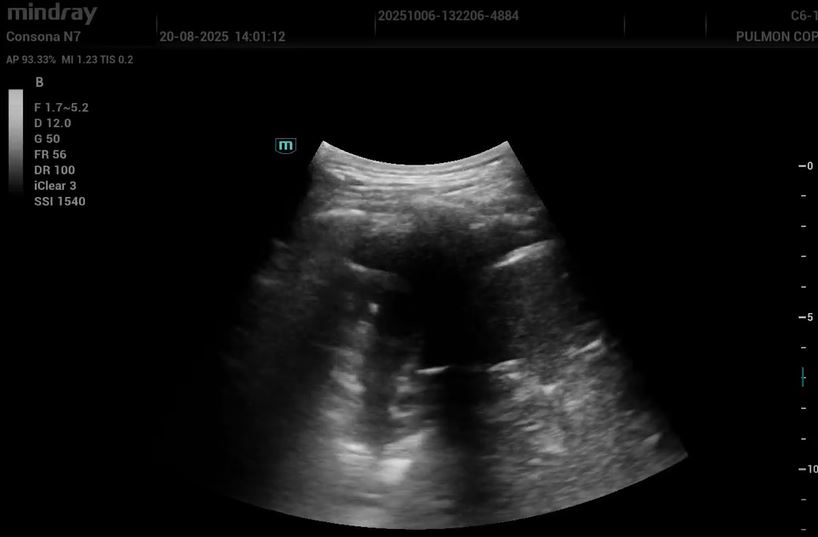

Hallazgos ecográficos

Eco pulmonar: colección anecoica con pérdida parcial del deslizamiento; compatible con derrame pleural de cuantía moderada.

Inicialmente, diagnóstico ecográfico de rotura fibrilar, manejo conservador. Posteriormente, ante dolor pleurítico y hallazgo ecográfico de derrame, primera derivación a Urgencias. Tras persistencia clínica, solicitud de Dímero D y segunda derivación como sospecha de TEP. Ingresa a cargo de Neumología iniciando anticoagulación con enoxaparina.